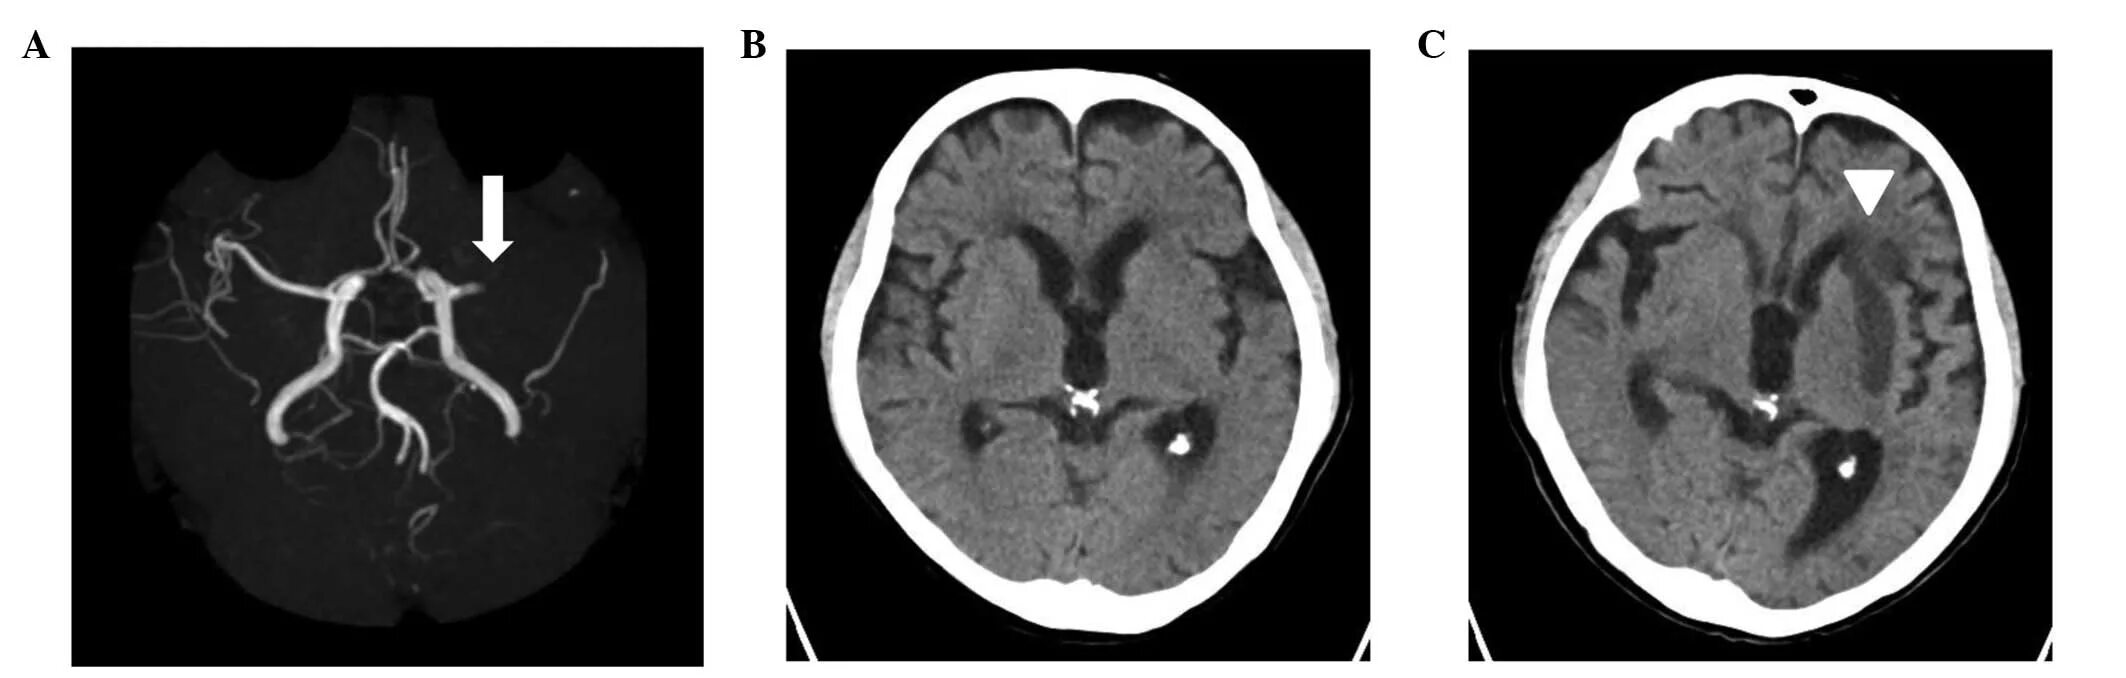

Аневризма головного мозга на кт